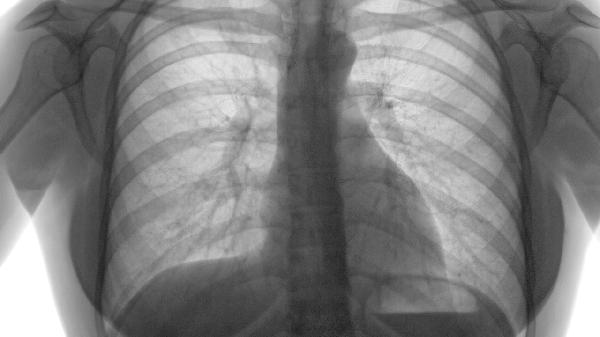

肺气肿患者出现脸肿腿肿可能与右心衰竭相关,需排查肺源性心脏病,主要诱因包括长期缺氧、肺动脉高压、心脏负荷加重、体液潴留及继发性肾功能异常。

肺气肿导致肺泡结构破坏,气体交换效率降低,血氧饱和度下降引发慢性缺氧。缺氧刺激肾脏分泌促红细胞生成素,血液黏稠度增加加重循环负担。治疗需通过长期低流量吸氧1-2L/min纠正缺氧,配合支气管扩张剂如沙丁胺醇气雾剂、噻托溴铵粉雾剂改善通气。

肺泡毛细血管床减少使肺血管阻力升高,右心室后负荷持续增加可发展为肺心病。超声心动图可检测肺动脉收缩压,治疗采用磷酸二酯酶-5抑制剂西地那非、内皮素受体拮抗剂波生坦或钙通道阻滞剂硝苯地平降低肺动脉压力。